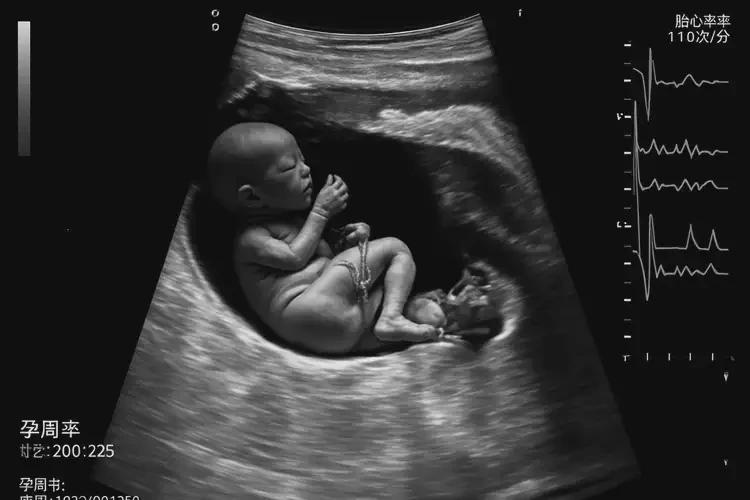

孕22周1天胎心率100有危險(xiǎn)嗎(圖1)

胎心率100次/分鐘在孕22周1天可能存在風(fēng)險(xiǎn)。正常情況下,孕22周的胎心率應(yīng)在120-160次/分鐘之間。胎心率低于120次/分鐘,尤其是低于100次/分鐘,可能表明胎兒存在缺氧或其他健康問題。

孕22周1天胎心率100有危險(xiǎn)嗎